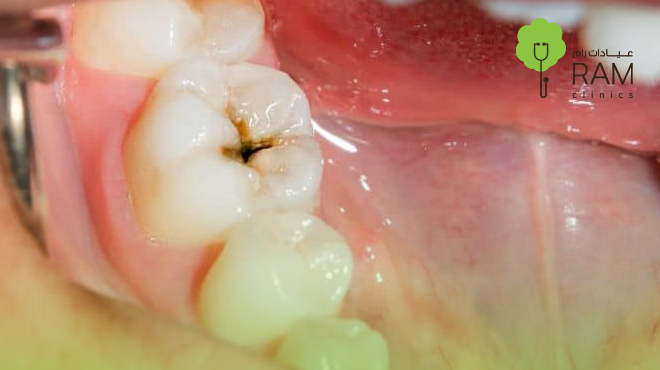

كيفية علاج الضرس المثقوب وأضرار إهماله: دليل شامل للتخلص من ألم الضرس المثقوب

الضرس المثقوب مشكلة شائعة تواجه الكثيرين، وقد يكون نتيجة لإهمال صحة الفم أو بسبب تناول الأطعمة الغنية بالسكر. تتنوع الأعراض بين ألم خفيف إلى شديد يصعب تحمله، لكن الأخبار الجيدة هي أن هناك طرقًا فعّالة لعلاج هذه المشكلة. في هذا المقال، سنتعرف على كيفية علاج الضرس المثقوب، ونناقش اضرار الضرس المثقوب، وأفضل الطرق لـالتخلص من الم الضرس المثقوب بشكل نهائي.

الضرس المثقوب هو حالة يتآكل فيها مينا الأسنان بسبب البكتيريا، مما يؤدي إلى ظهور فجوة أو ثقوب صغيرة أو كبيرة في السن. إذا لم يتم علاج هذه المشكلة في مراحلها الأولى، يمكن أن تتفاقم لتصل إلى العصب، مسببة ألم الضرس المثقوب ألمًا حادًا ومضاعفات خطيرة.